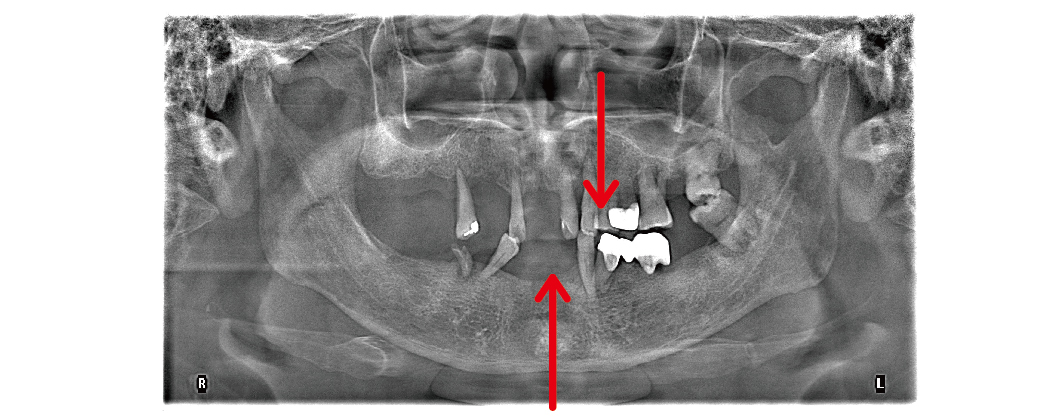

治療流程大致上會分成幾個步驟。首先,我們會幫您做完整的評估,包括拍 X 光、3D 電腦斷層、口內數位照片,確認骨頭的狀況和適合的位置。

▲箭頭處為長期使用活動假牙,造成咬合不便、牙齒鬆動